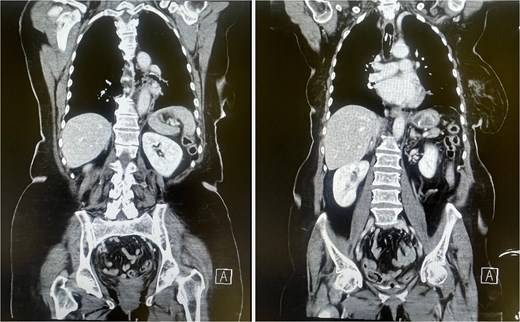

After repeat endoscopy (Fig. 1) and CT (Fig. 2) confirmed a 10 cm perforation with mediastinal air, emergency surgery was performed. A cervical-abdominal approach was used to resect the perforated esophagus and relieve the obstruction. Intraoperatively, extensive adhesions and a cholecystoduodenal fistula were found. Jejunal concretions and the impacted stone at the ligament of Treitz was removed. En bloc resection of the gallbladder and cholecystoduodenal fistula was performed and the duodenal defect was closed in two layers. A T-drain was inserted into the common bile duct and a percutaneous endoscopic gastrostomy tube was introduced for enteral feeding. The esophagus was circumferentially mobilized via a transhiatal approach and resected in discontinuity up to the esophagogastric junction, with the proximal esophagus exteriorized as a cervical esophagostomy. Postoperatively, the patient was transferred from the intensive care unit to the general ward on postoperative day three. All intraoperatively placed drains were removed in a timely manner due to unremarkable output. The postoperative course was otherwise unremarkable, and the patient was released into rehabilitative care.

CT scan showing mediastinal air consistent with esophageal perforation (left) and a hyperdense structure in the stomach corresponding to the gallstone within the Dormia basket (right).